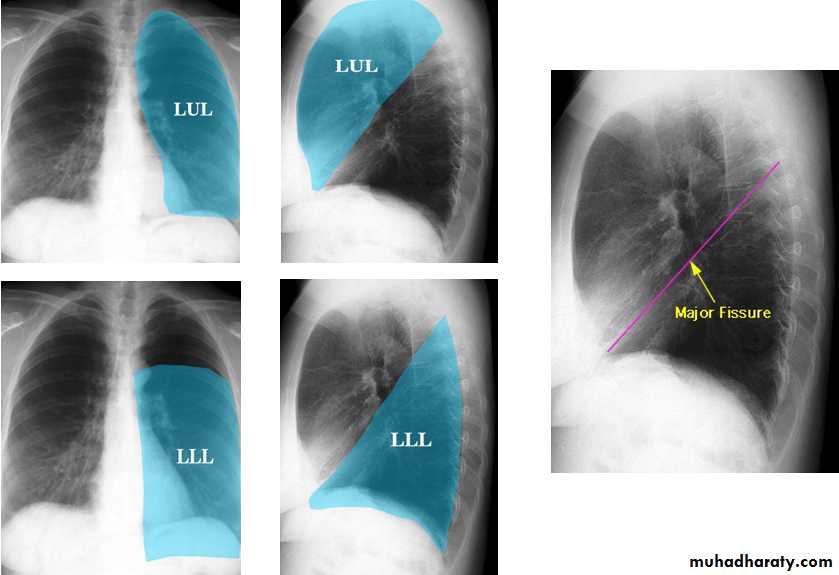

Radiologic anatomy of the RT lung lobes

Radiologic anatomy of the LT lung lobes

Lobes and fissures

This cut-out of a lateral chest x-ray shows the positions of the lobes of the right lung

On the left the oblique fissure is in a similar position but there is usually no horizontal fissure, and so there are only two lobes on the left.